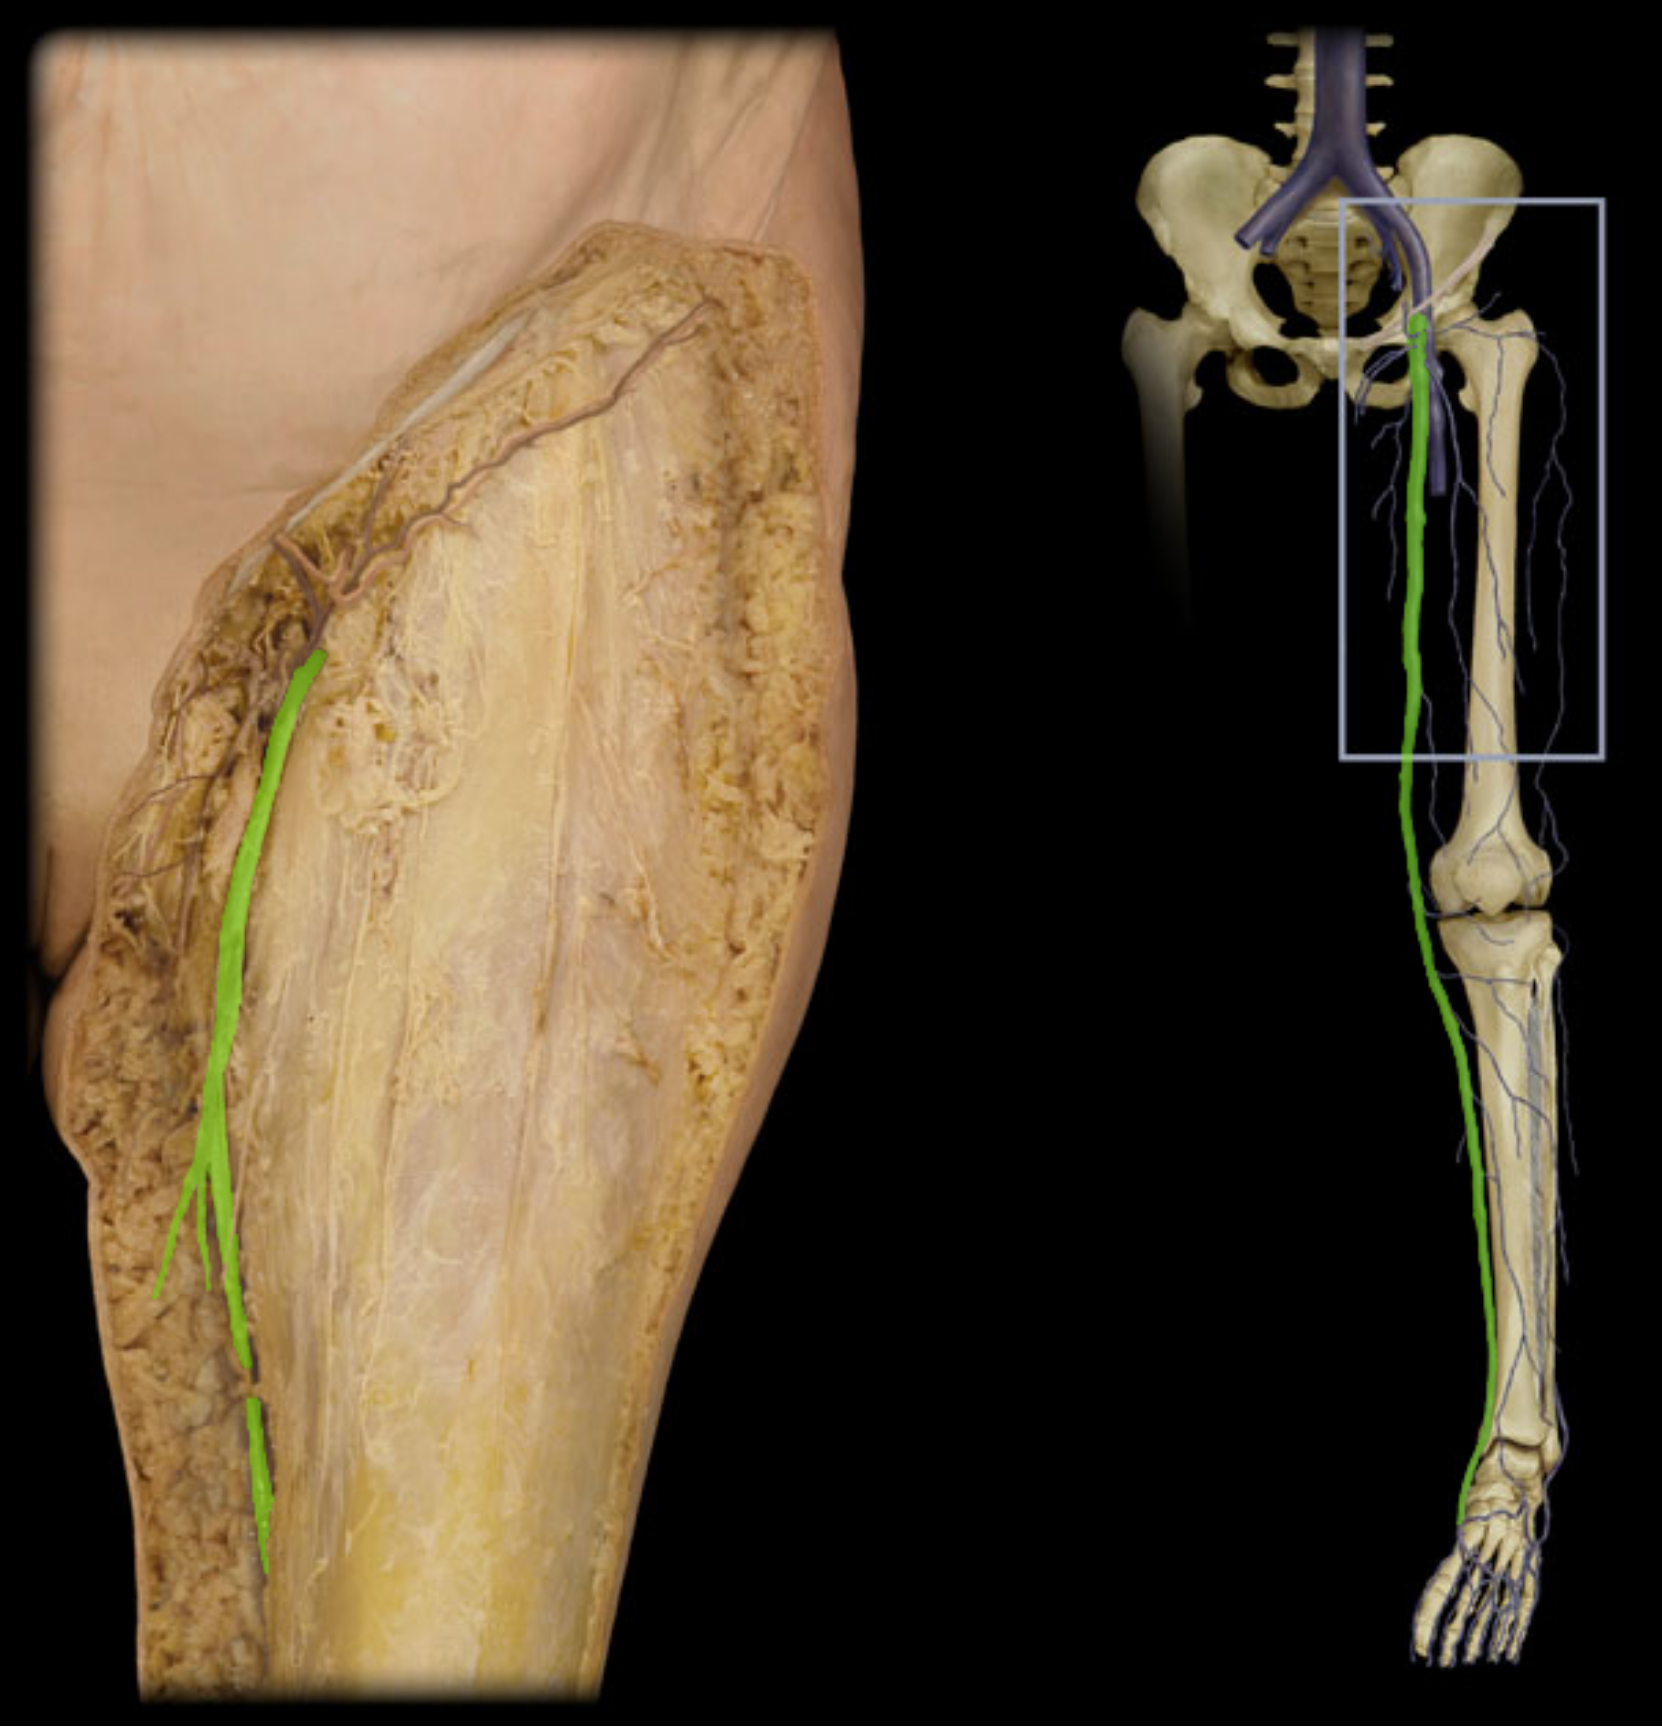

Femoral v.

Great saphenous v.